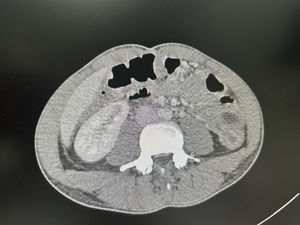

Se realiza ecografía de abdomen (fig. 1) en la que se objetiva inflamación de la pared del intestino grueso (flecha roja) con un grosor de 1,45cm (valor normal 0,3cm) y ausencia de peristaltismo visualizado en vídeo en comparación con el asa de intestino delgado (flecha azul), hallazgos compatibles con colitis que posteriormente se confirma por TC (fig. 2).